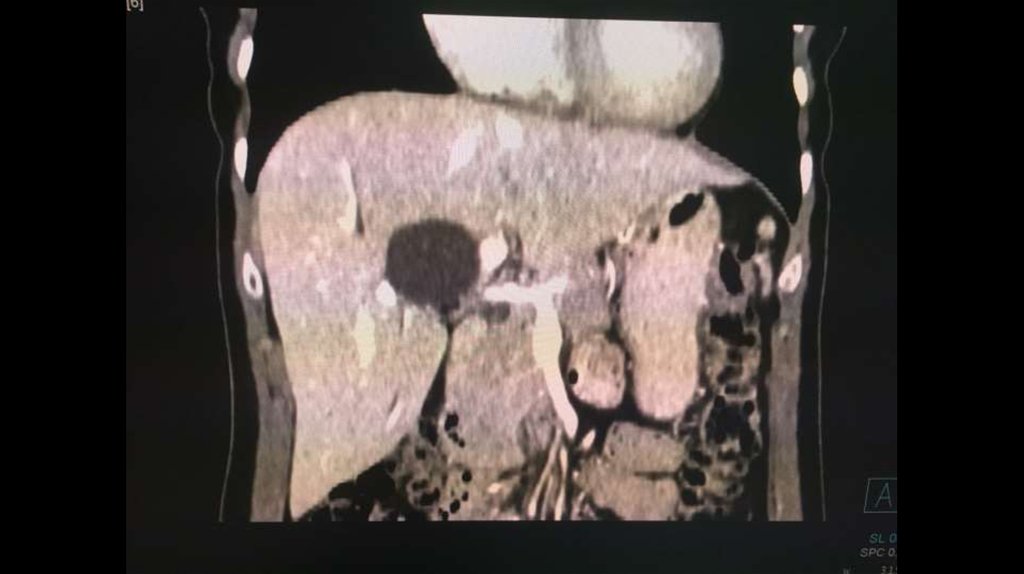

По направлению из ЦГБ в ККБ №1 поступил пациент М., 48 лет, с диагнозом «Эхинококкоз

печени»

Пациенту в плановом порядке выполнено КТ ОБП. По результатам исследования выявлена

эхинококковая киста IV-V сегментов.